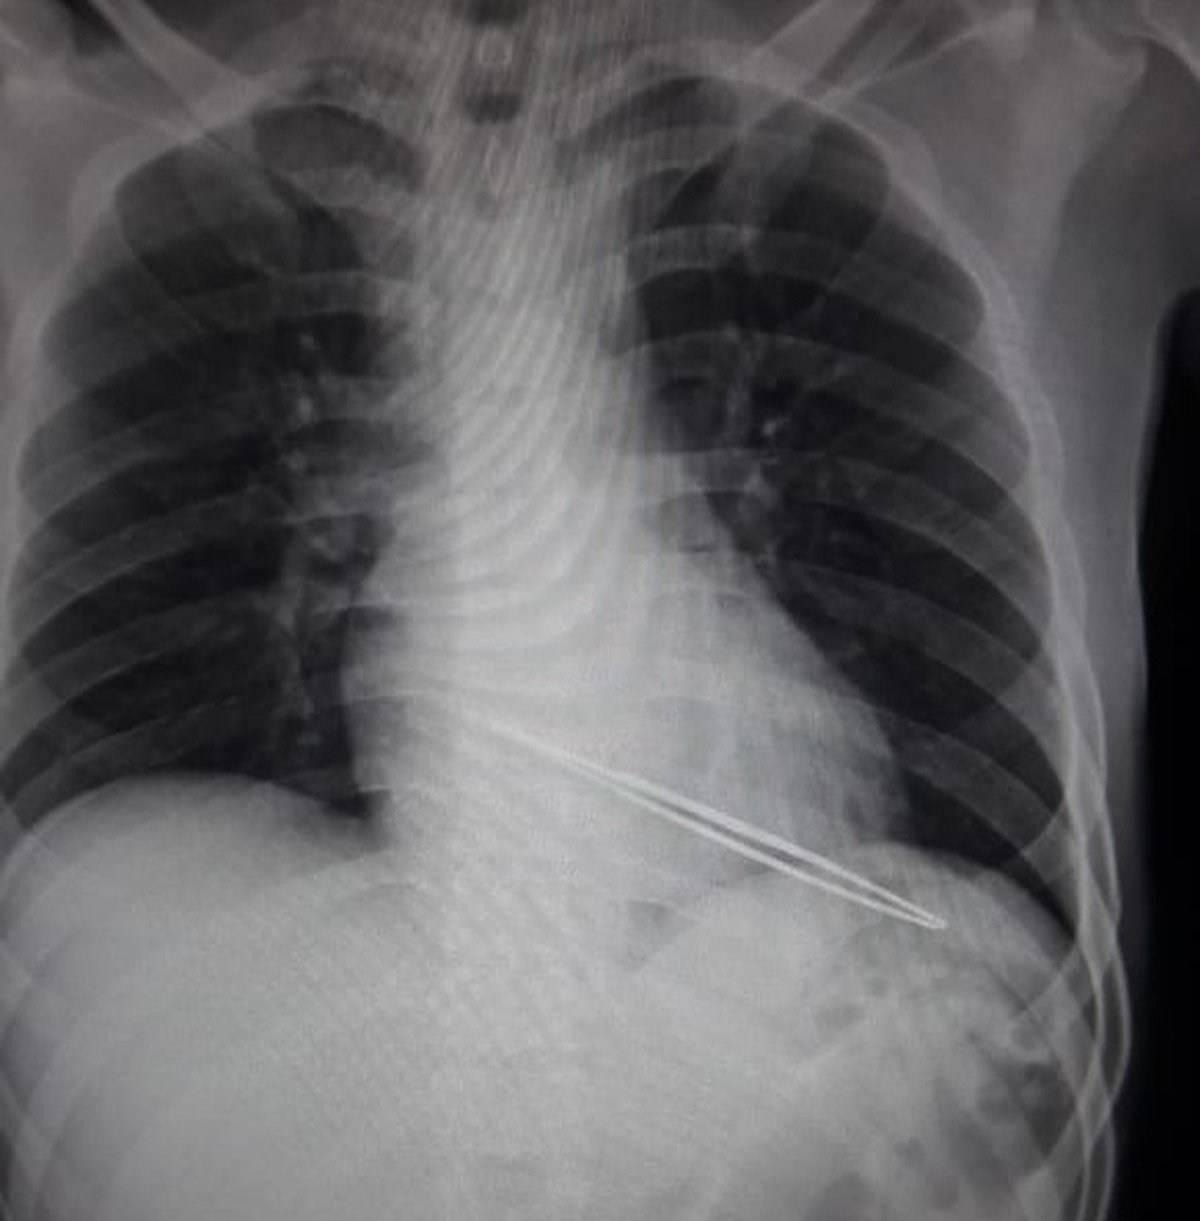

Ainda segundo o delegado, a lâmina da faca usada tinha menos de quatro centímetros. O rapaz morreu de hemorragia no hospital.

“Foi um único golpe bem em cima do coração. Não achamos a faca, foi apreendida só a bainha que estava no bolso dele. Não acho que seja homicídio, acredito que foi lesão seguida de morte. Deu um golpe e saiu”, explicou.